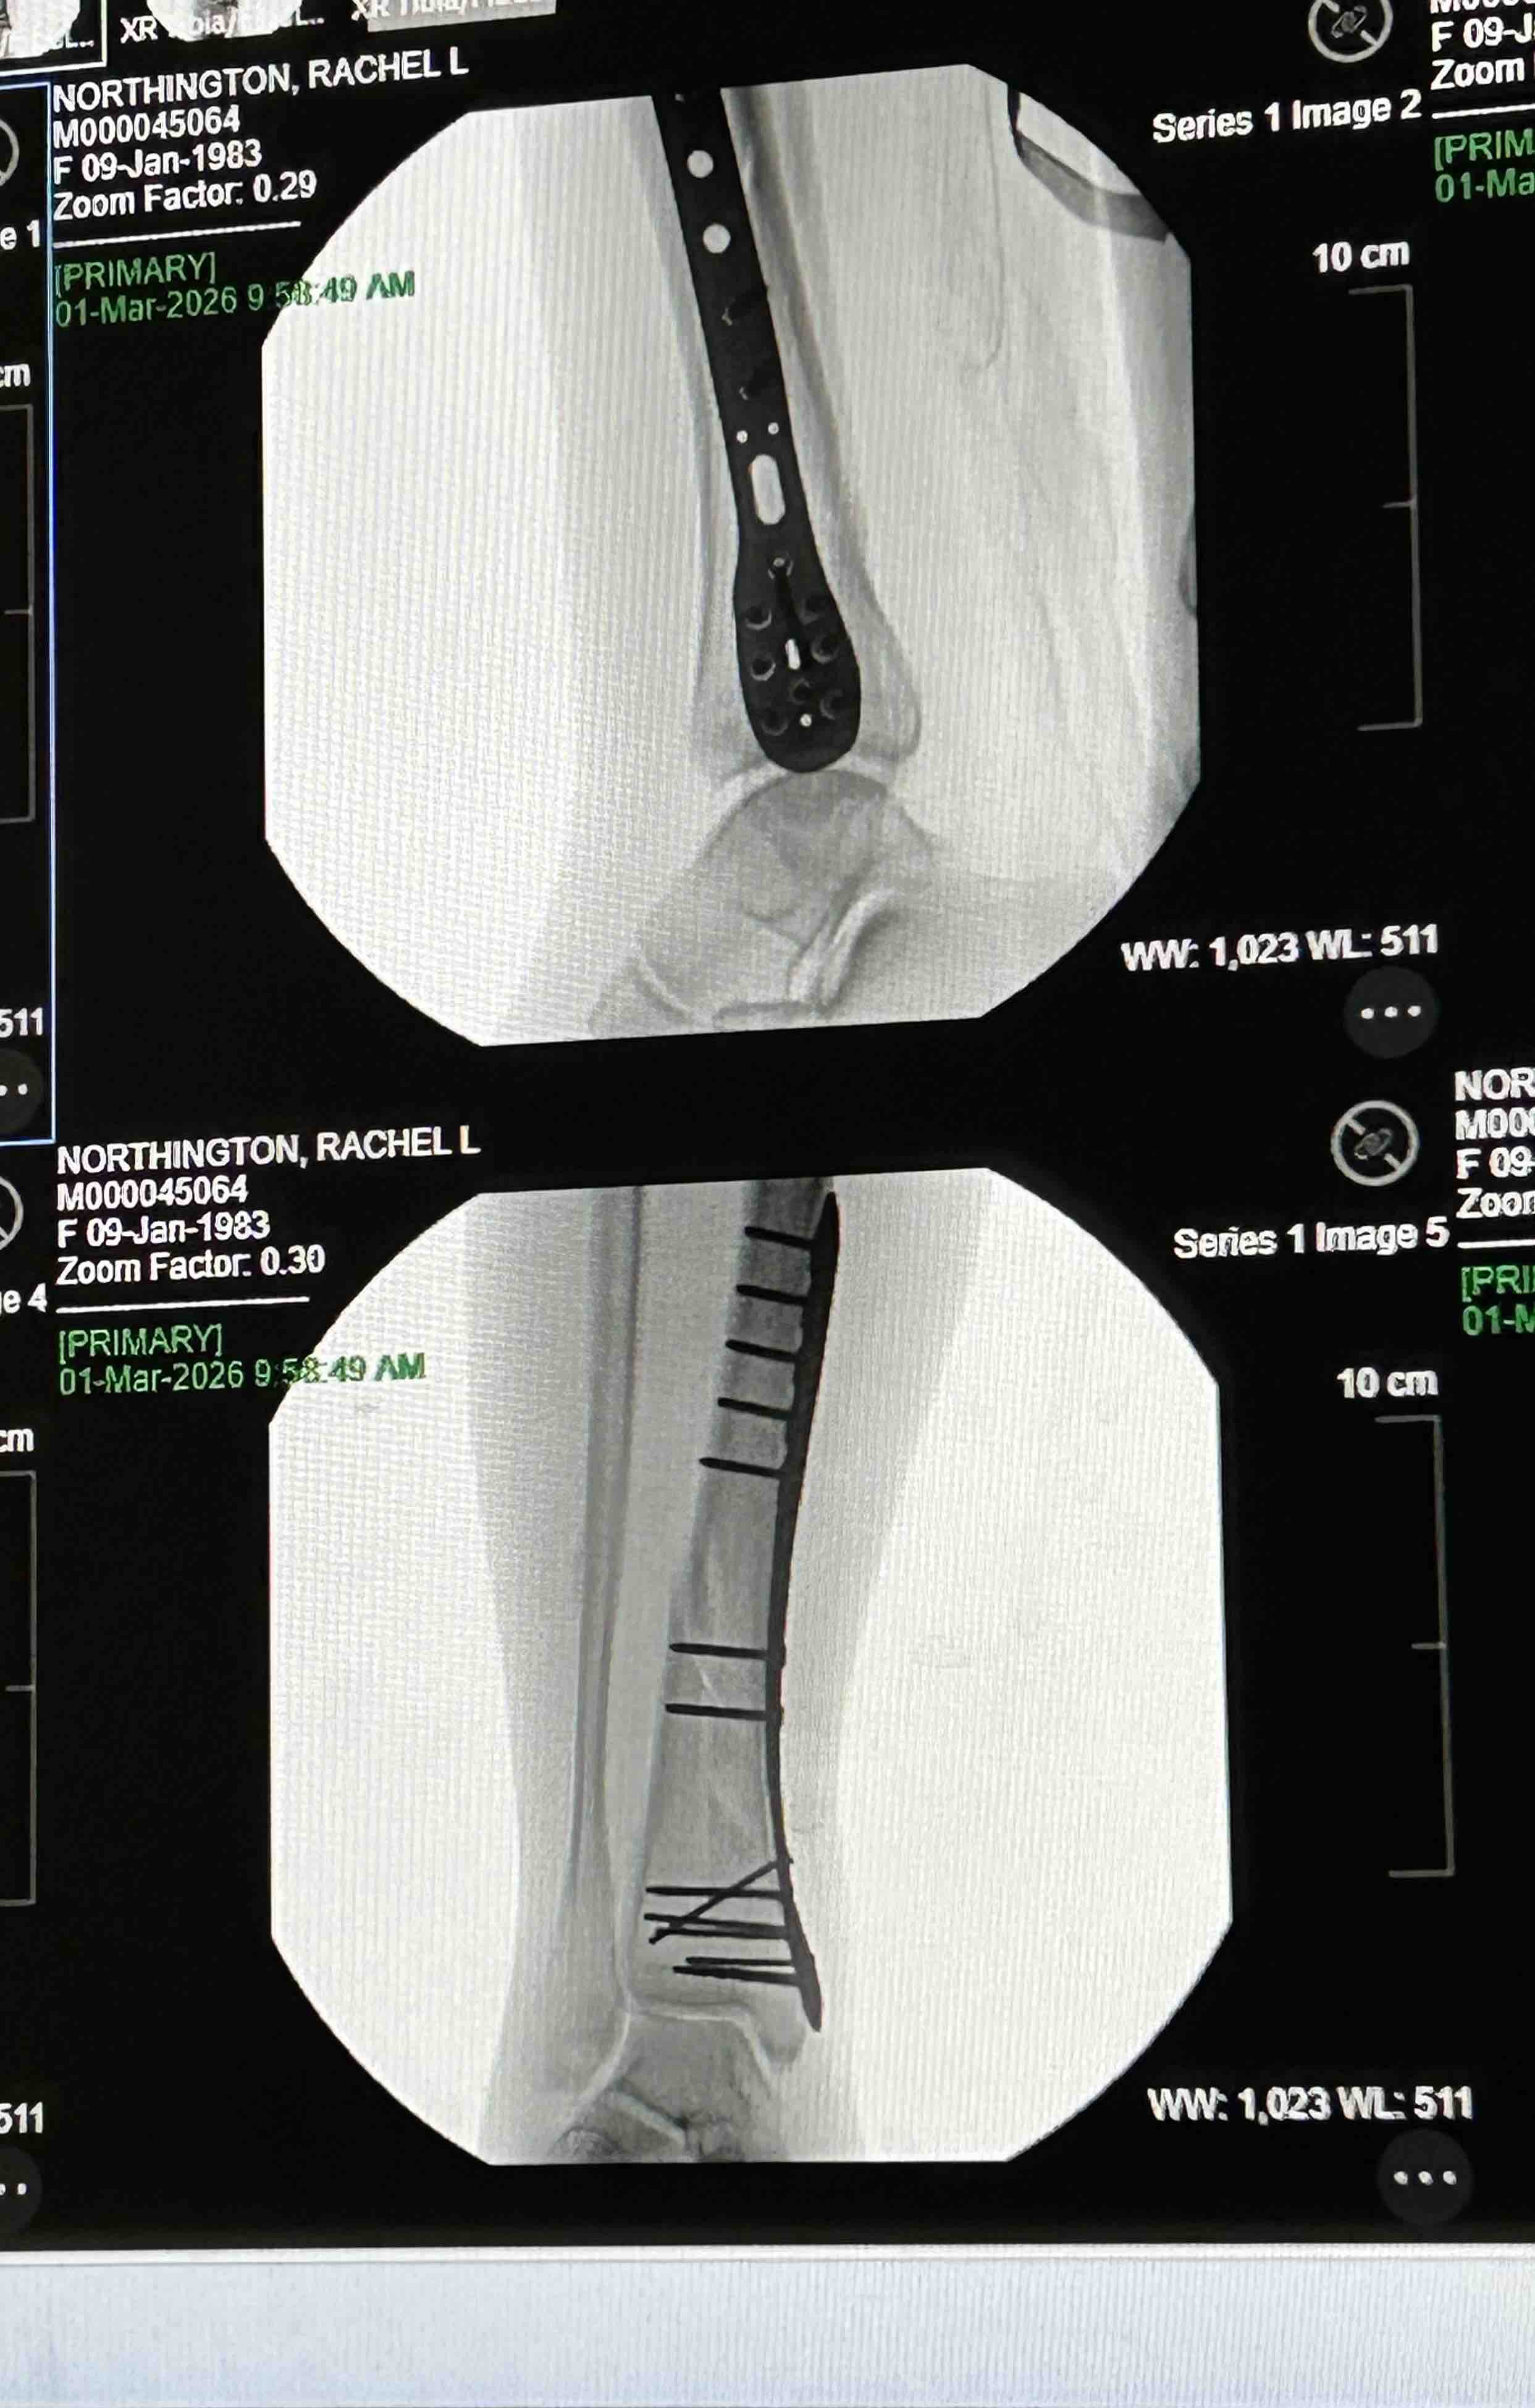

Hello my name is Rachel and I’m usually a pretty active and healthy girl. I was taken to the Murray Hospital February 15th and discharged on the 24th due to severe pancreatitis and pneumonia. I was home only a couple days and still felt very weak and tired. I attempted to go into my bathroom and somehow lost my footing and my whole body landed on my right leg and broke my right tibia and fibula (8.0 cm severely comminuted fracture of the proximal fibular shaft and 10.2 cm spiral fracture distal tibial shaft). 2 very bad fractures . It was the worst pain I’ve ever experienced! It took me 30 mins to crawl about 30 feet to my bed where my phone was to call 911 for help. The paramedics wouldn’t let me look at my leg and kept telling me to try to just lay down and relax, which was extremely hard to do. I was told my leg looked crooked and my foot was turned all the way to the side. With the help of the fire department, I was able to make it down my steps and to the ER. I had 2 doctors come in while in the ER and reset it the best they could until I could have surgery. Was supposed to be the next day but a special plate and screws had to be sent to the hospital so Sunday morning at 8am, an hour long surgery took almost 3. I now have a 9 inch place and 13 screws in my leg on one of the fractures. Depending on how the other fracture looks when I see my Ortho for follow up, I may need another surgery to put a plate on it as well. I am non weight bearing for 6-8 weeks and won’t be able to drive for no earlier than 6 months. Full recovery is a year or more. Since I am not currently working, I have applied and talked to many people about getting some sort of disability to help me keep my apartment but not getting a lot of good answers so far. I have even had my doctors send in letters stating my condition and how severe it is but it’s not getting anywhere. If anyone could find it in their heart to help me stay above water, I would greatly appreciate it!! Even a couple dollars goes a long way! All money will go to medical expenses including physical therapy, doctor appointments, medicine and the rental of medical equipment I need to get around. I didn’t want to have to make this but I’m in a rough place right now and could really use the help. Any help is appreciated. Thank you and God Bless!